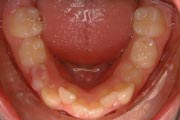

Crowding

Before